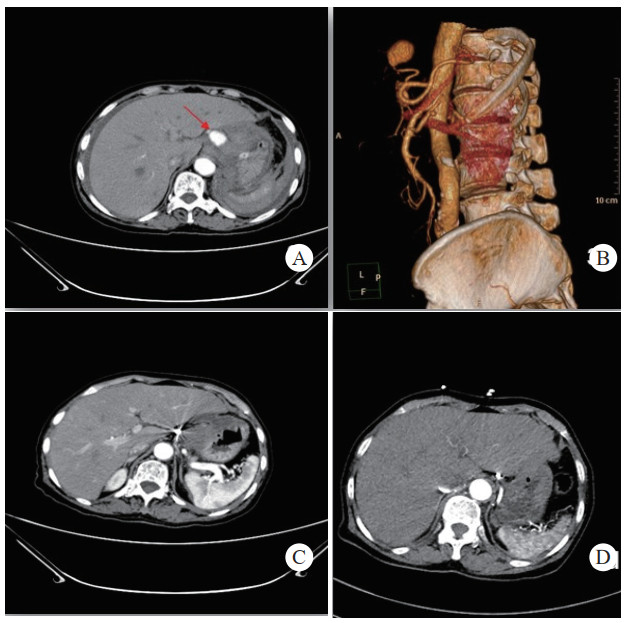

治疗后随诊复查CT显示,患者载瘤动脉及瘤腔内可见栓塞弹簧圈,血肿、假性动脉瘤瘤体体积明显缩小,未见血管再通与假性动脉瘤破裂,见图 2(病例2)。

| 注:图 2病例2 A为患者术前CT增强扫描,示胰腺炎影像,腹腔内见一血肿影,脾动脉起始段可见一瘤样扩张,内见对比剂填充;B、C分别为患者术后3 d及术后1个月复查CT增强示,血肿较前减小,原瘤样扩张处可见弹簧圈影及未见对比剂外溢 图 2 病例2术前、术后CT平扫及增强 |

患者经介入栓塞治疗后,长期的随访CT及增强CT中,未出现责任动脉或瘤体再次发生破裂导致二次出血、弹簧圈移位及血栓异位栓塞等并发症,见图 3(病例3)。

| 注:A、B为患者术前CT增强扫描及血管重建技术,示胰腺炎影像,腹腔内见一血肿影,内可见与动脉强化一致的动脉瘤影像(箭头示),其供血动脉为胃左动脉;C为患者术后三天复查CT增强扫描,示血肿较前吸收减小,内见弹簧圈影及未见对比剂外溢。D为患者术后三年复查CT增强示,血肿消失,原动脉瘤处可见弹簧圈影及未见对比剂外溢 图 3 病例3术前、术后CT平扫及增强 |